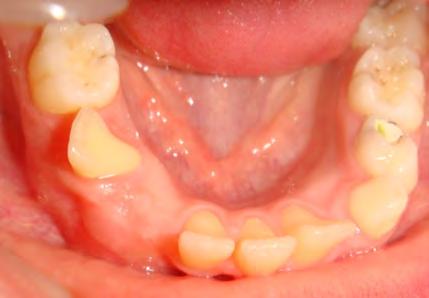

Below are cases treated at Vakresmil without extractions within the last three years. The families had been told, “It is simply not possible for your child to be treated without extractions” by orthodontists. Judge for yourself if that was right or wrong.

The overall aim is to produce the best smile we can — a “beautiful smile”, if you will — without premolar extractions, headgear, facemasks or banded appliances. A smile that both the patient and we at Vakresmil can be proud of.